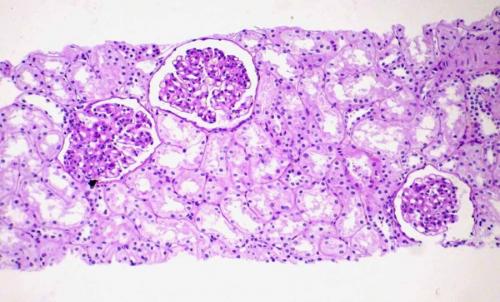

Одним из негативных последствий алкоголизма является нарушение экскреторной функции почек. Проще говоря, орган теряет способность к выведению продуктов обмена, в результате чего происходит их накопление в организме. Это может вызывать массивное отравление и возникновение алкогольной нефропатии — гибели почечных клубочков.

Недавние клинические и экспериментальные исследования показали, что привычное употребление большого количества этанола оказывает пагубное воздействие на почки.

У пациентов с хроническим алкоголизмом описаны различные дефекты канальцев. Дисфункция канальцев играет важную патофизиологическую роль в широком спектре электролитных и кислотно-щелочных нарушений, обычно наблюдаемых у этих пациентов, и, возможно, при остеопорозе. Эти повреждения почек часто обратимы и исчезают при отказе от спиртного. Однако с 1990 года сообщалось о нескольких случаях синдрома острого канальцевого некроза из-за приема этанола при отсутствии других очевидных нефротоксических механизмов или при отсутствии связи с применением нестероидных противовоспалительных препаратов – анальгетической нефропатии .

Кроме того обнаружены следующие факты:

- выявлена связь между гломерулонефритом и алкоголизмом;

- при вскрытии у 64% хронических алкоголиков была продемонстрирована IgA-нефропатия;

- обнаружена связь между алкоголизмом и постинфекционным гломерулонефритом;

- все чаще при алкогольном синдроме плода, наблюдаемом у детей, которые пренатально подвергались воздействию этанола, встречаются структурные и функциональные аномалии почек.